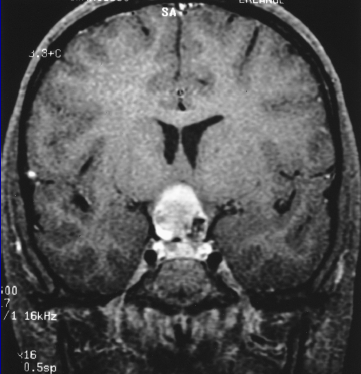

PEDS CNS: Crainiopharyngioma

Craniopharyngiomas are epithelial tumors arising from the remenants of Rathke's pouch in the suprasellar region. They are benign tumors.

Craniopharyngiomas most frequently arise in the suprasellar region, or the sella proper (less common). Although benign, they become problematic due to local progression around critical structures. Tumors becme increasingly problematic due to their spatial location, abutting the third ventricle causing increased intracranial pressure.

Craniopharyngiomas appear as partially calcified and cystic lesions on CT and MRI. Biopsy confirmation is not absolutely necessary for the diagnosis of craniopharyngiomas. Diagnosis can be made based on imaging findinga and cystic fluid analysis. There is no formal staging other than the degree of grading based on th amount of hypothalamic invasion.